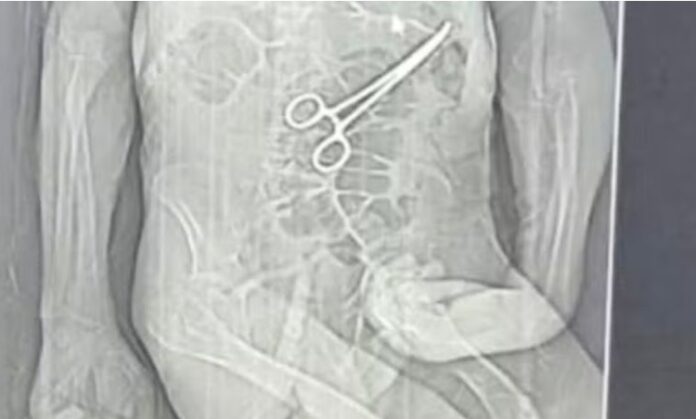

Segundo familiares, exames realizados após um segundo procedimento identificaram uma pinça do tipo “Kelly” dentro do corpo do paciente. A Secretaria Municipal de Saúde confirmou o caso e informou que abriu sindicância para apurar responsabilidades, alegando que o paciente apresentava quadro grave e múltiplas comorbidades. A família, no entanto, contesta e afirma que o erro médico foi determinante para a morte.